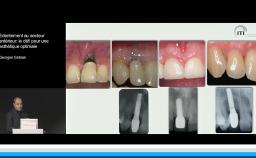

Cette présentation s’intéresse à l’influence des étapes chirurgicales sur le résultat esthétique en implantologie.

Tous les types d’implants peuvent être utilisés en secteur antérieur, mais l’utilisation de connexions au niveau osseux offre plus de latitude sur le placement de l’implant et sur la réhabilitation prothétique. Afin de limiter les proximités entre implants et entre dents et implants, l’utilisation d’implants de faible diamètre et la réduction du nombre d’implants sont des options à considérer.